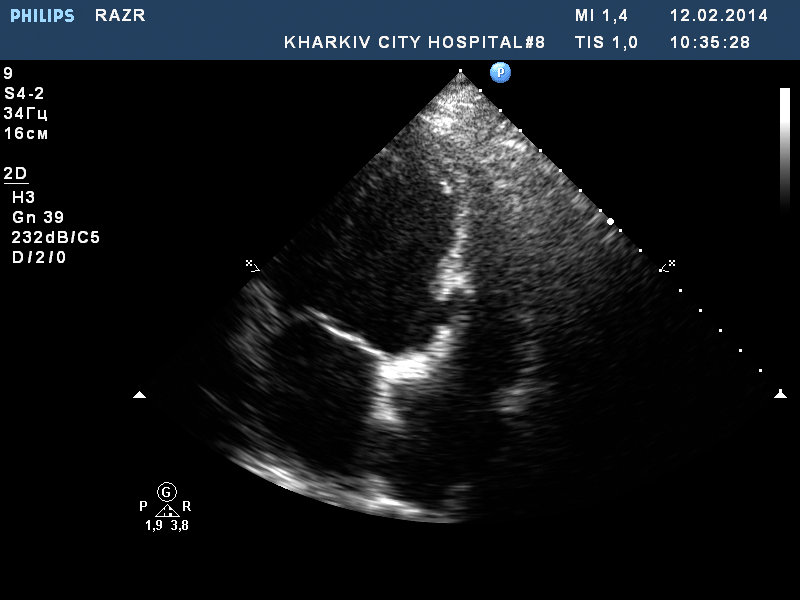

У данного пациента состояние после пластики разрыва МЖП (несколько лет назад на фоне инфаркта), решунт до 3.0мм по ширине потока, дилатация левых полостей, акинезия базальных нижнего, нижне-перегородочного,заднего сегментов левого желудочка, гипертрофия левого желудочка.